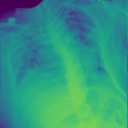

4.1.2 Lung Segmentation

Additionally, we evaluate the performance of DiffeoNN on real-world data, using a dataset with chest X-ray images and their ground-truth lung segmentation from (RSUA, 2023). The original dataset contains images and corresponding ground-truth segmentations into three different classes (“Non-Covid”, “Covid”, and “Non-Covid-Pneumonia”). We combine the images and corresponding ground-truth segmentations of the initial three classes into one dataset, which is then split into a training dataset of image-segmentation pairs, a validation dataset of pairs, and a test dataset of pairs. We then proceed as in Section 4.1.1 to create a dataset of diffeomorphically transformed images.

We apply DiffeoNN, the inner U-Net (naïve approach) and an augmented U-Net, which is trained on the original and the diffeomorphically transformed training dataset, to the diffeomorphically transformed images from the test dataset. Visual results are presented in Figure 4 and further details on the experimental setup, training, and additional examples in Appendix B. The results closely mirror those obtained on the synthetic dataset, see Table 1(b). On average, DiffeoNN outperforms the naïve approach, validating the effectiveness of our approach. The canonicalisation step pushes the input image towards the training dataset by moving the thorax to a more central position and aligning the shoulders, which makes it easier for the inner U-Net to predict an accurate lung segmentation. While our method performs slightly below the augmented gold-standard baseline, it offers more flexibility by not relying on data augmentation or retraining, making it a practical and robust solution in real-world applications.

| Input | Canonicalised Input | Segmentation of | Output DiffeoNN | Output Naïve U-Net | Output Augmented U-Net | Ground-Truth Segmentation |